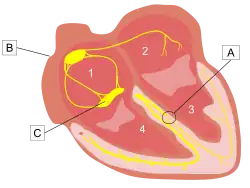

The heart's electrical activity begins in the sinoatrial node (the heart's natural pacemaker), which is situated on the upper right atrium. The impulse travels next through the left and right atria and summates at the atrioventricular node. From the AV node the electrical impulse travels down the bundle of His and divides into the right and left bundle branches. The right bundle branch contains one fascicle. The left bundle branch subdivides into two fascicles: the left anterior fascicle, and the left posterior fascicle. Other sources divide the left bundle branch into three fascicles: the left anterior, the left posterior, and the left septal fascicle. The thicker left posterior fascicle bifurcates, with one fascicle being in the septal aspect. Ultimately, the fascicles divide into millions of Purkinje fibres, which in turn interdigitate with individual cardiac myocytes, allowing for rapid, coordinated, and synchronous physiologic depolarization of the ventricles.

When a bundle branch or fascicle becomes injured (by underlying heart disease, myocardial infarction, or cardiac surgery), it may cease to conduct electrical impulses appropriately. This results in altered pathways for ventricular depolarization. Since the electrical impulse can no longer use the preferred pathway across the bundle branch, it may move instead through muscle fibers in a way that both slows the electrical movement and changes the directional propagation of the impulses. As a result, there is a loss of ventricular synchrony, ventricular depolarization is prolonged, and there may be a corresponding drop in cardiac output. When heart failure is present, a specialized pacemaker may be used to resynchronize the ventricles. In theory a pacemaker like this will shorten the QRS interval, thus bringing the timing of contraction of the left and right ventricles closer together and slightly increasing the ejection fraction.